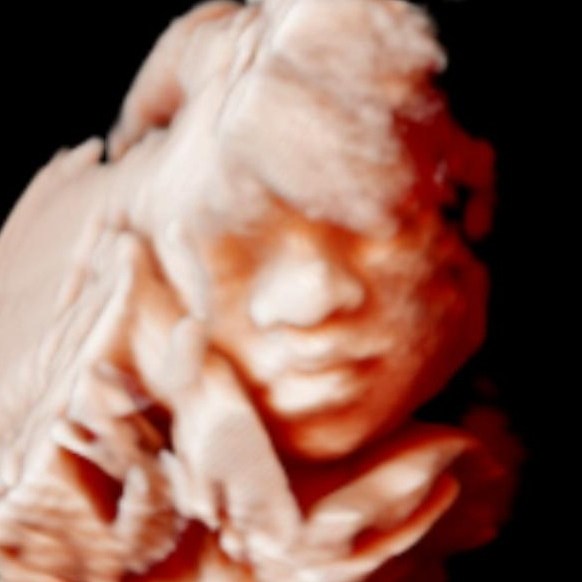

- Echographie de datation, du 1er/2ème/3ème trimestre, croissance, 3D/4D